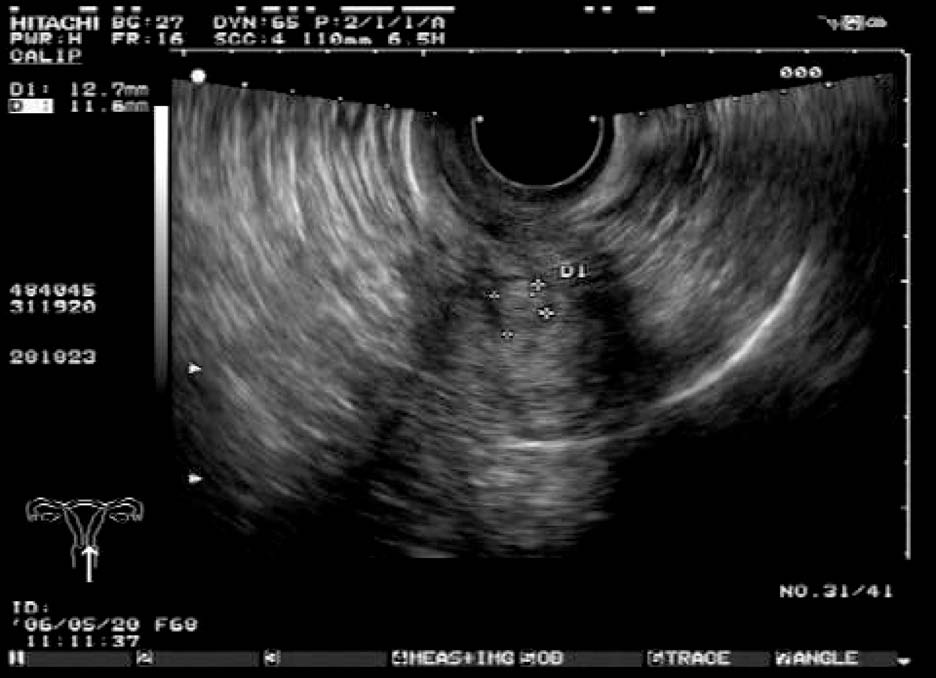

患者,女,42岁,常规体检。超声检查声像图显示:子宫前位,三径正常,边界清,子宫内膜欠清。肌内可见多个低回声包块,较大者约1.7cm×1.4cm(前壁)、1.8cm×1.4cm(前壁)、1.9cm×1.4cm(后壁),边界清,有假包膜,内部回声均匀,子宫边界规整。CDFI探查:较大团块周围见半环状彩色血流信号。包块内未见彩色血流信号。宫腔内可见节育器影像,距宫底约1.5cm。

超声提示:子宫肌瘤(肌间);宫内节育器,位置正常。